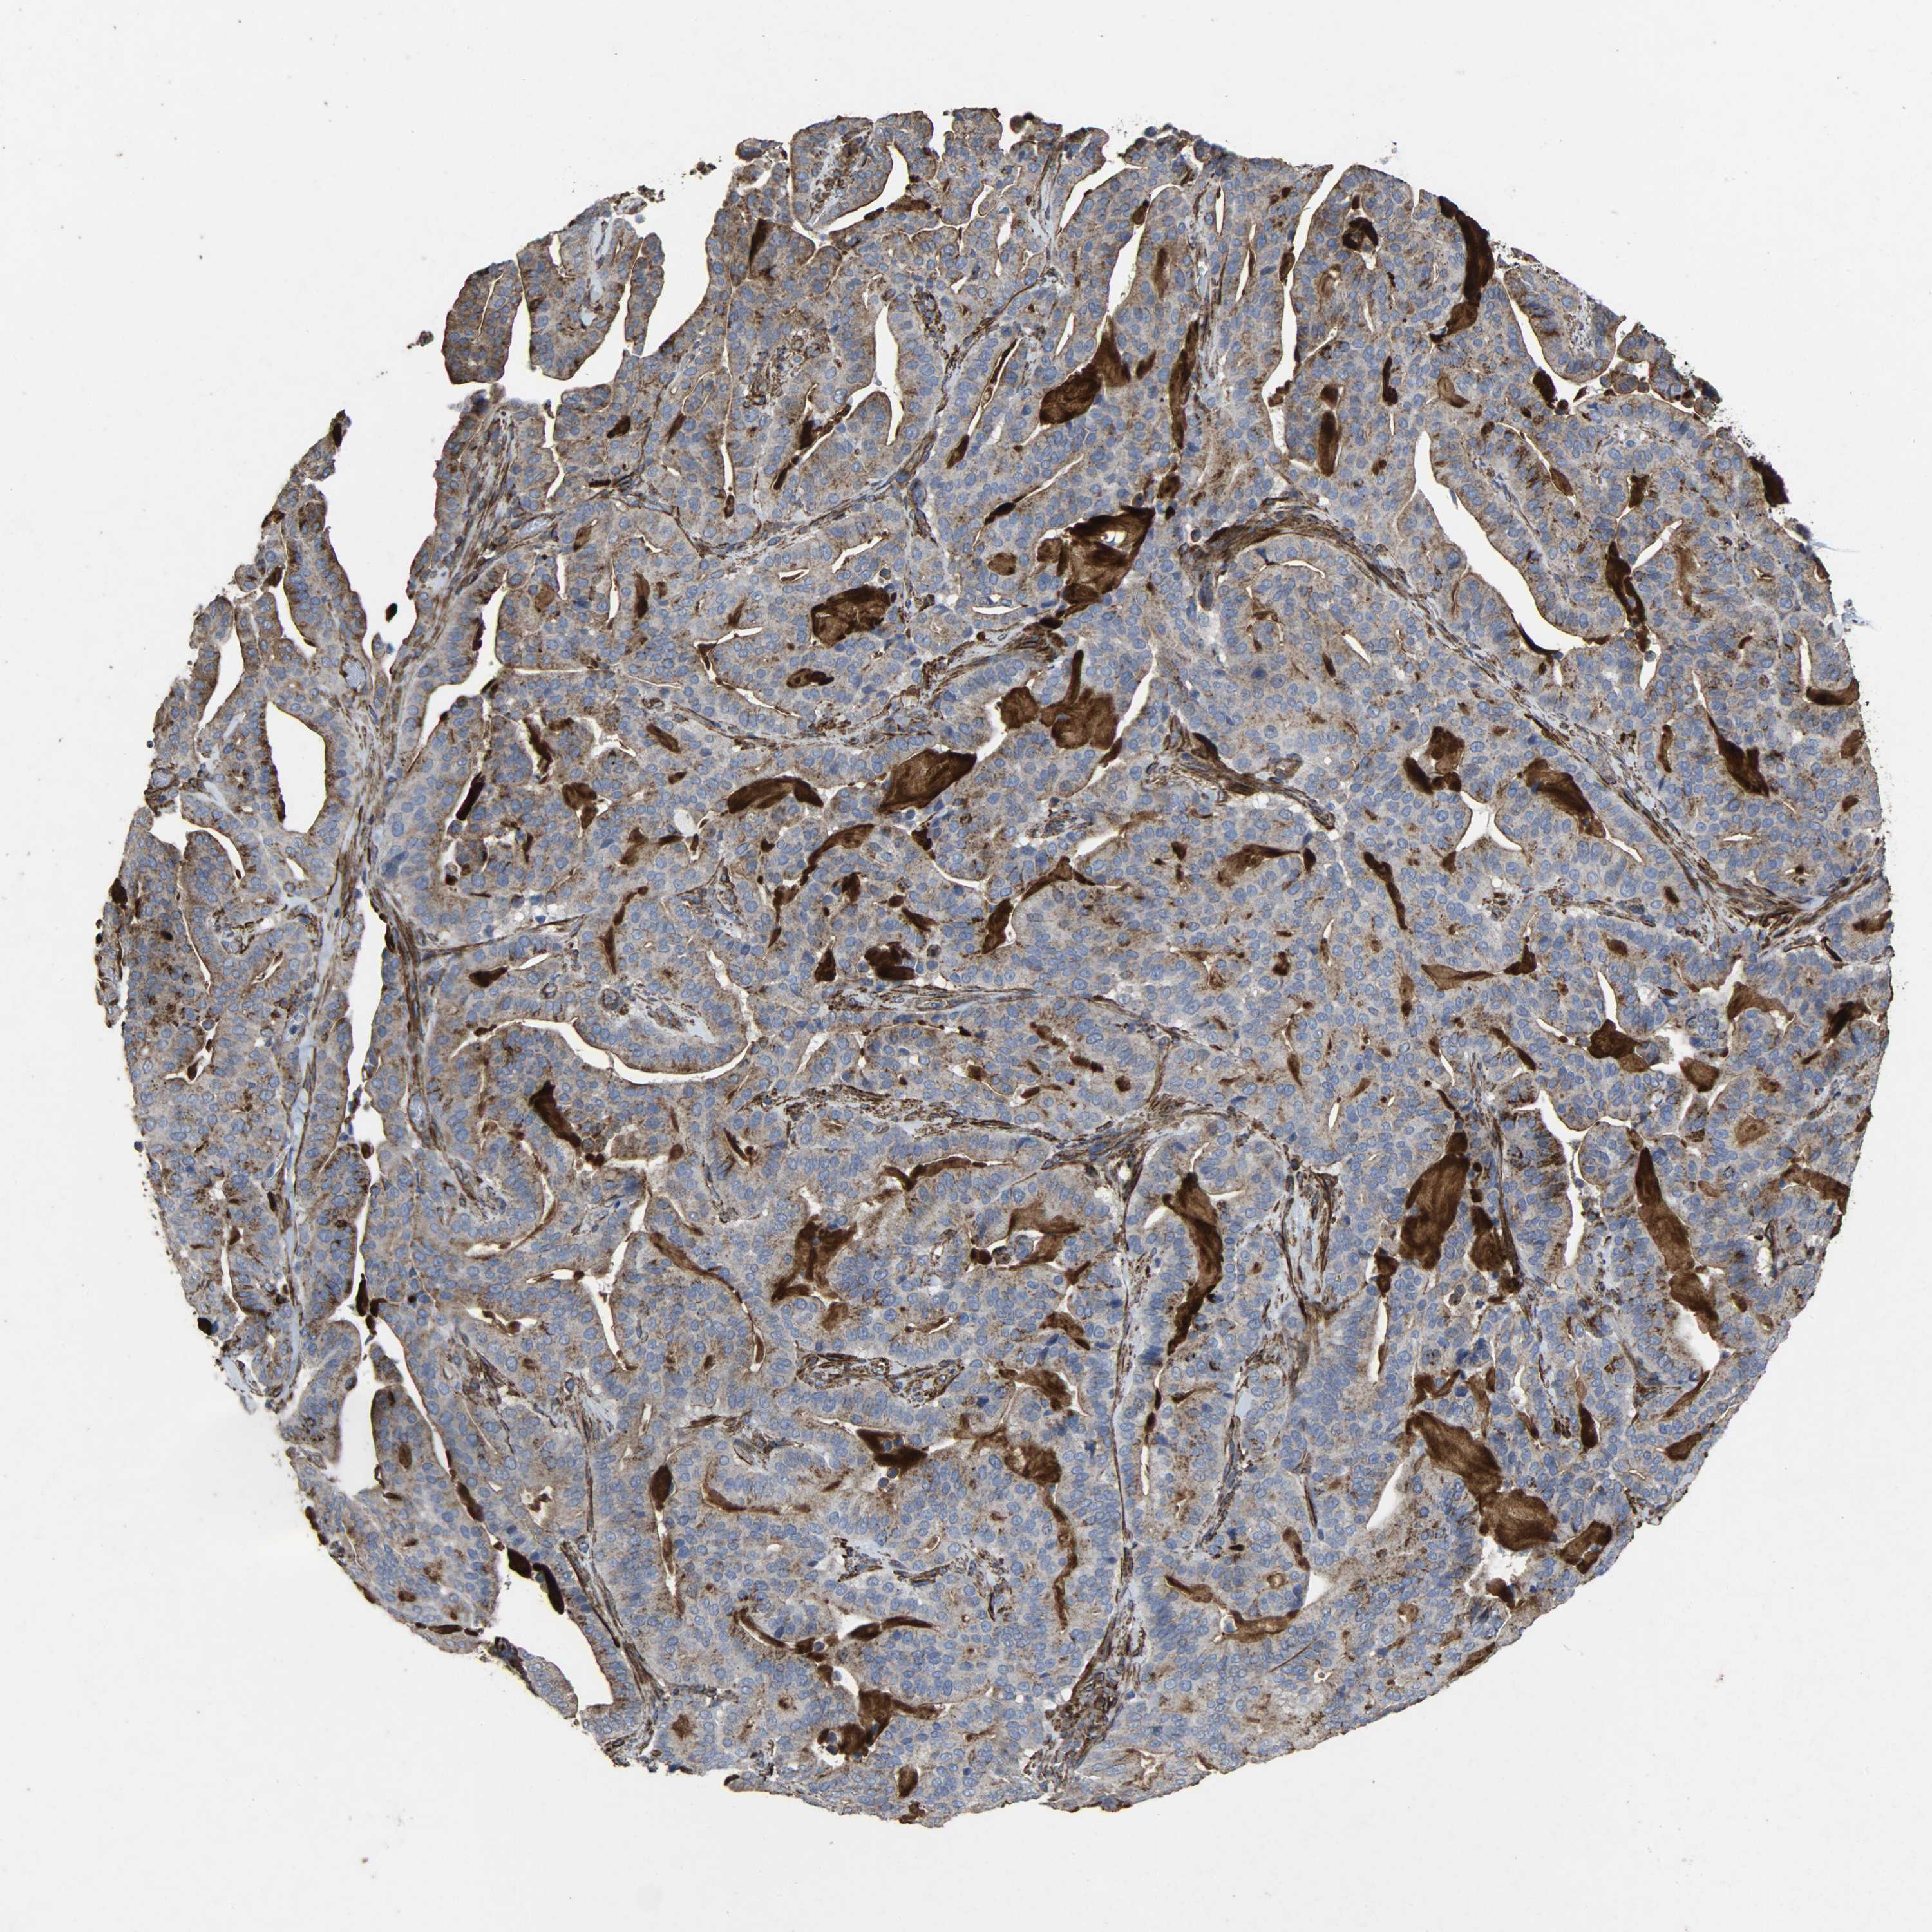

PANCREATIC CANCER - Protein expressioni

A mouse-over function shows sample information and annotation data. Click on an image to view it in a full screen mode. Samples can be filtered based on level of antibody staining by selecting one or several of the following categories: high, medium, low and not detected. The assay and annotation is described here.

Note that samples used for immunohistochemistry by the Human Protein Atlas do not correspond to samples in the TCGA dataset.

Antibody stainingi

Antibody staining in the annotated cell types in the current human tissue is reported as not detected, low, medium, or high, based on conventional immunohistochemistry profiling in selected tissues. This score is based on the combination of the staining intensity and fraction of stained cells.

Each image is clickable and will lead to virtual microscopy that enables deeper exploration of all samples and also displays staining intensity scores, fraction scores and subcellular localization as well as patient and tissue information for each sample.

Antibody HPA047089

Antibody HPA053624

Antibody CAB004685

Staining

High

Medium

Low

Not detected

Intensity

Strong

Moderate

Weak

Negative

Quantity

>75%

75%-25%

<25%

None

Location

Nuclear

Cytoplasmic/membranous

Cytoplasmic/membranous,nuclear

Adenocarcinoma, NOS

Adenocarcinoma, metastatic, NOS